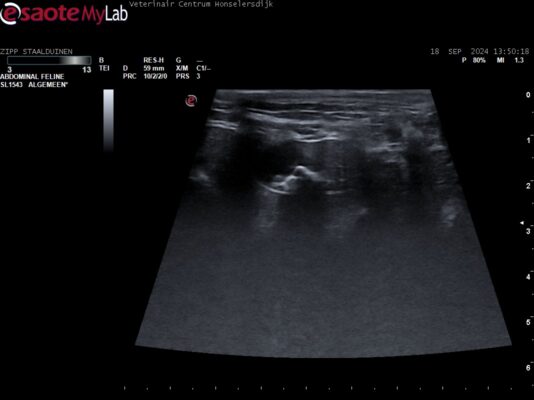

Karin Lunenborg startte de discussie galstenen in het forum Moeilijke klinische Cases: Laat Je Helpen! Samen Kunnen we Meer! een jaar geleden

Ik heb vandaag een kat gezien, Heilige Birmaan, Mk, 13 jaar. Deze kat is door mijn op de metacam gezet vanwege arthroseklachten en een paar weken later is een klein panel biochemie gedaan om te kijken of dat goed ging. Er waren geen specifieke klachten die aanleiding daarvoor gaven. Wel braakt deze kat al jaren wekelijks waar nooit iets mee…